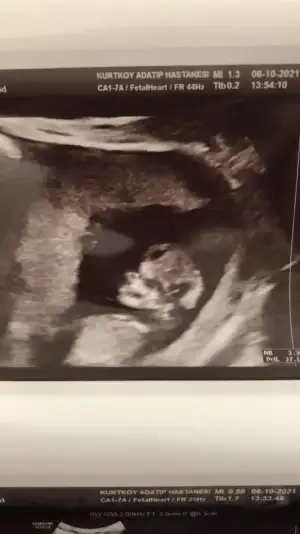

dr soylemeden siz gorun genital nub teorisi ( bebegin cinsiyeti)

Doktor cinsiyet için erken dedi söylemedi ama ben çok merak ediyorum bakar mısınız

IMG-20210927-WA0034.webp

• IMG-20210927-WA0035.webp

IMG-20210927-WA0035.webp